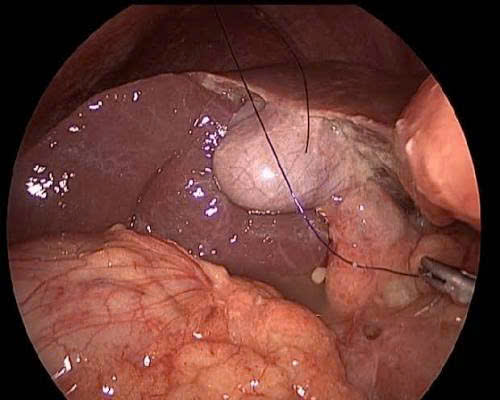

Trung tâm Y tế Khu vực Thuận An vừa tiếp nhận bệnh nhân nam, 47 tuổi, tiền sử viêm dạ dày và lạm dụng rượu bia. Bệnh nhân nhập viện khẩn cấp với cơn đau bụng dữ dội, chẩn đoán thủng ổ loét dạ dày. Sau khi được phẫu thuật nội soi kịp thời, bệnh nhân đã ổn định.

Loét dạ dày là tình trạng tổn thương niêm mạc do mất cân bằng giữa các yếu tố bảo vệ (chất nhầy, bicarbonate) và các yếu tố tấn công (acid HCl, pepsin). Khi vết loét ăn sâu, xuyên qua thành dạ dày, dịch vị và vi khuẩn sẽ tràn vào khoang phúc mạc, gây viêm phúc mạc - một biến chứng nguy hiểm.

Thủng ổ loét dạ dày là một cấp cứu ngoại khoa. Việc chẩn đoán và phẫu thuật sớm là yếu tố quyết định sự sống còn của bệnh nhân. Những người có tiền sử viêm loét dạ dày, hoặc thường xuyên sử dụng rượu bia, thuốc chống viêm không steroid (NSAID) cần đặc biệt lưu ý các dấu hiệu trên để được cấp cứu kịp thời.